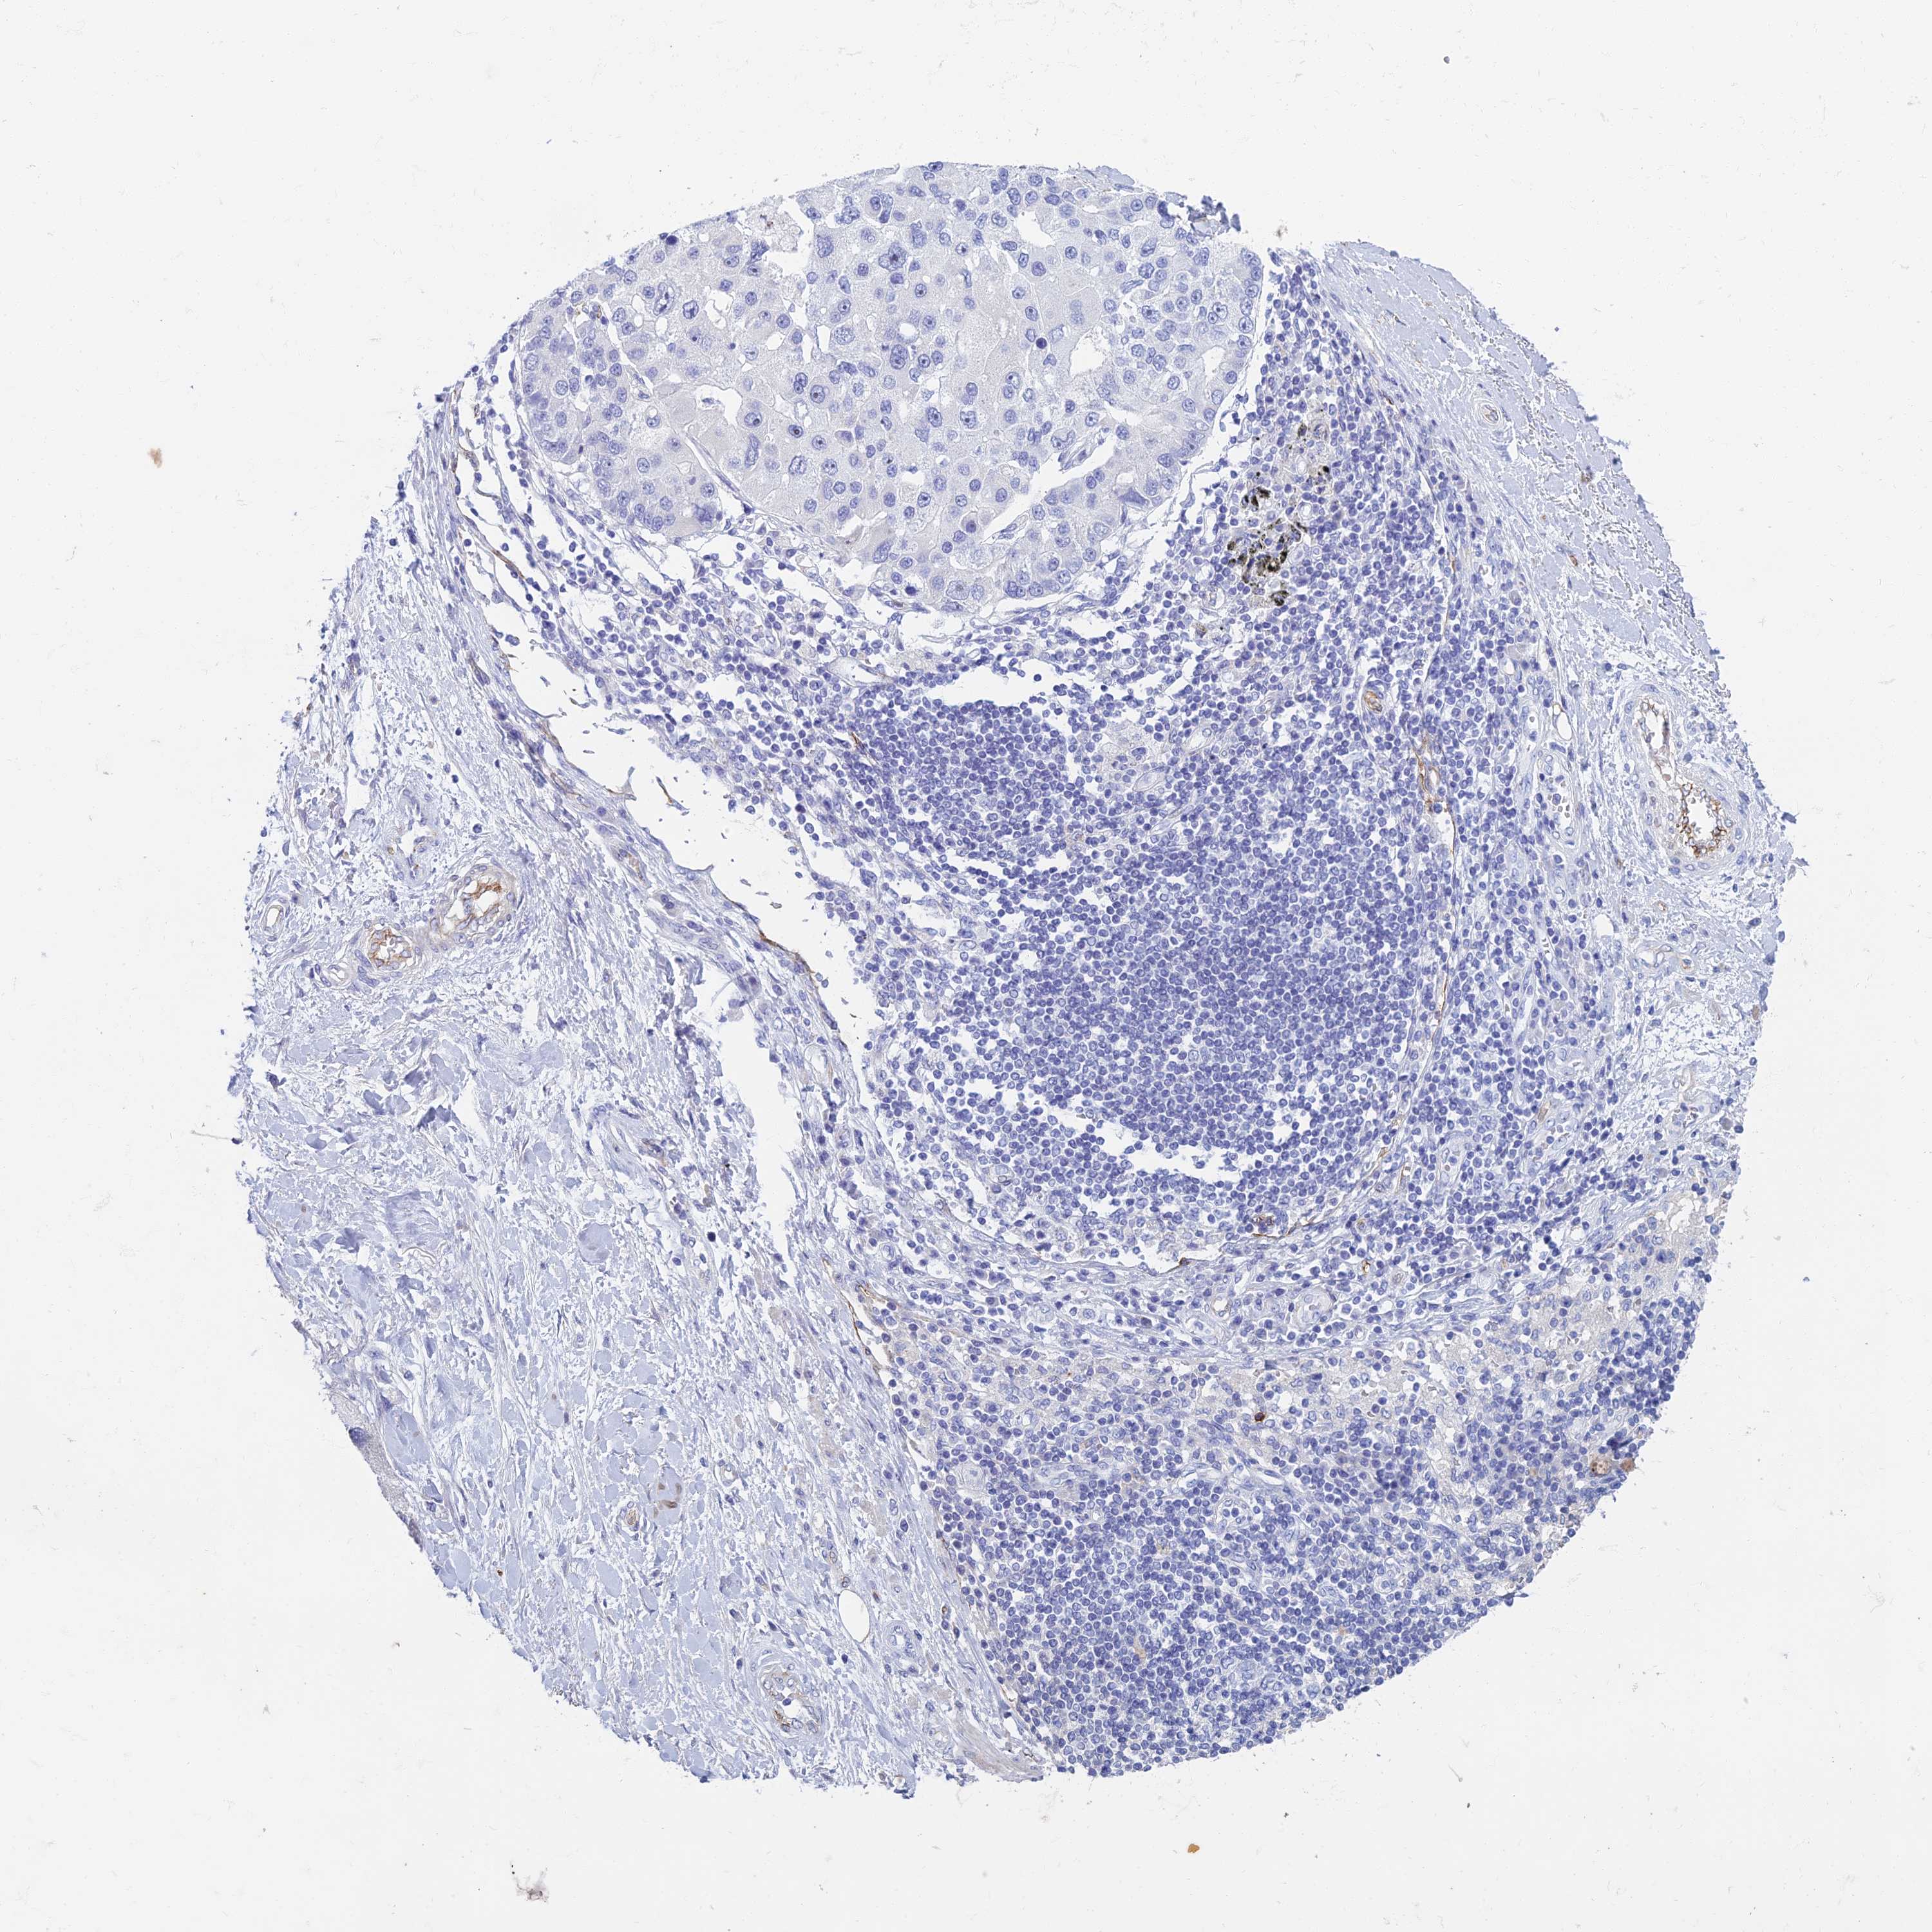

CANCER LUNG CANCER Show tissue menu

ETFRF1 is not prognostic in Lung Adenocarcinoma (TCGA)